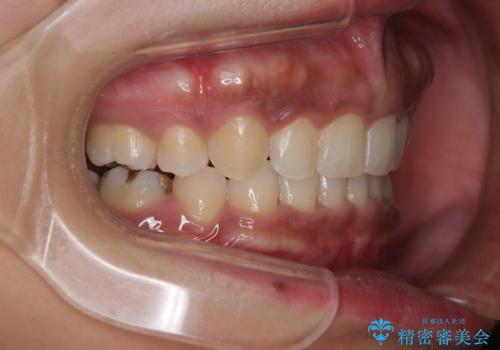

- 治療期間

- 3年6ヶ月

- 治療回数

- 30回以上